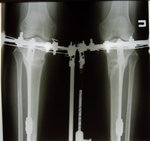

В процессе исправления.

20141128_110512.jpg